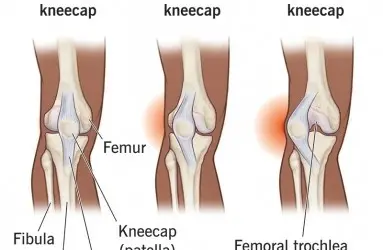

- Diz Ekleminde Kireçlenme (Diz Osteoartriti)

- Diz Protezi